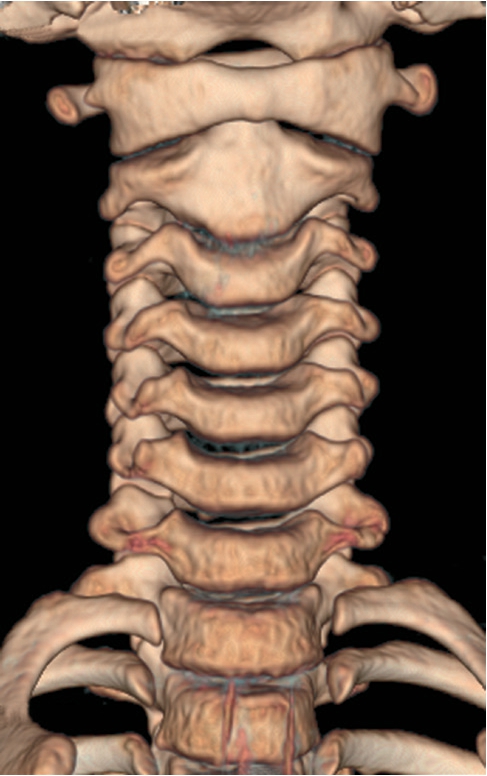

2.CT优势 通过薄而连续的切面图,多排螺旋CT扫描速度快,具有较高的图像分辨率,运用重建技术得到冠状位、矢状位及斜位图像,通过图像后期处理功能进行三维重建(图7-1-1),便于观察、分析病灶内部情况、复杂的解剖结构以及重叠位置的病变。

图7-1-1 颈椎CT三维重建